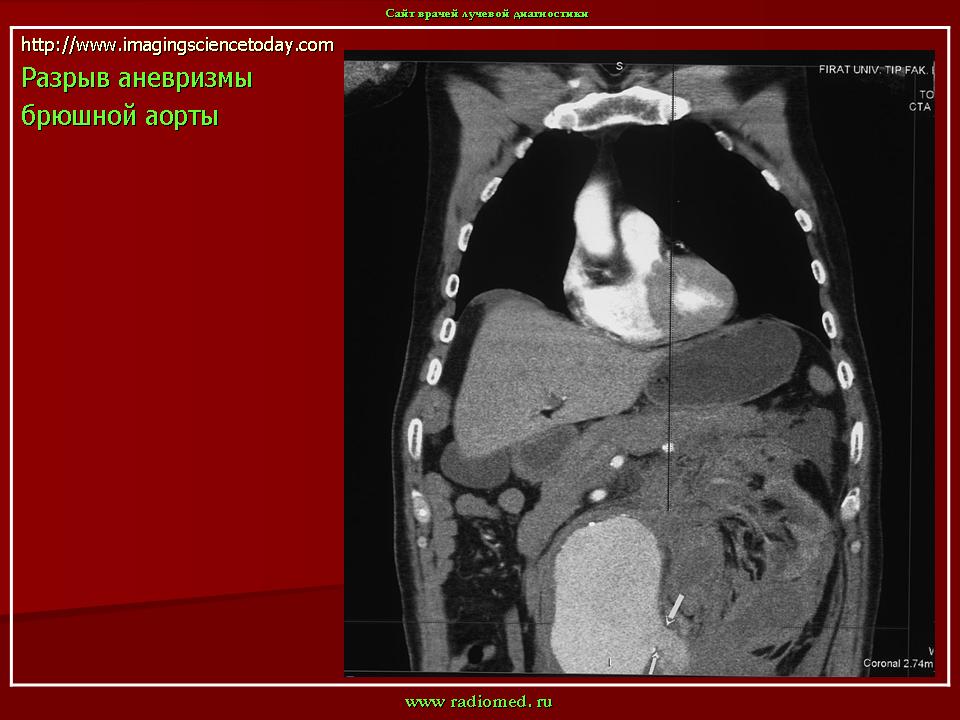

Аневризмы брюшной аорты